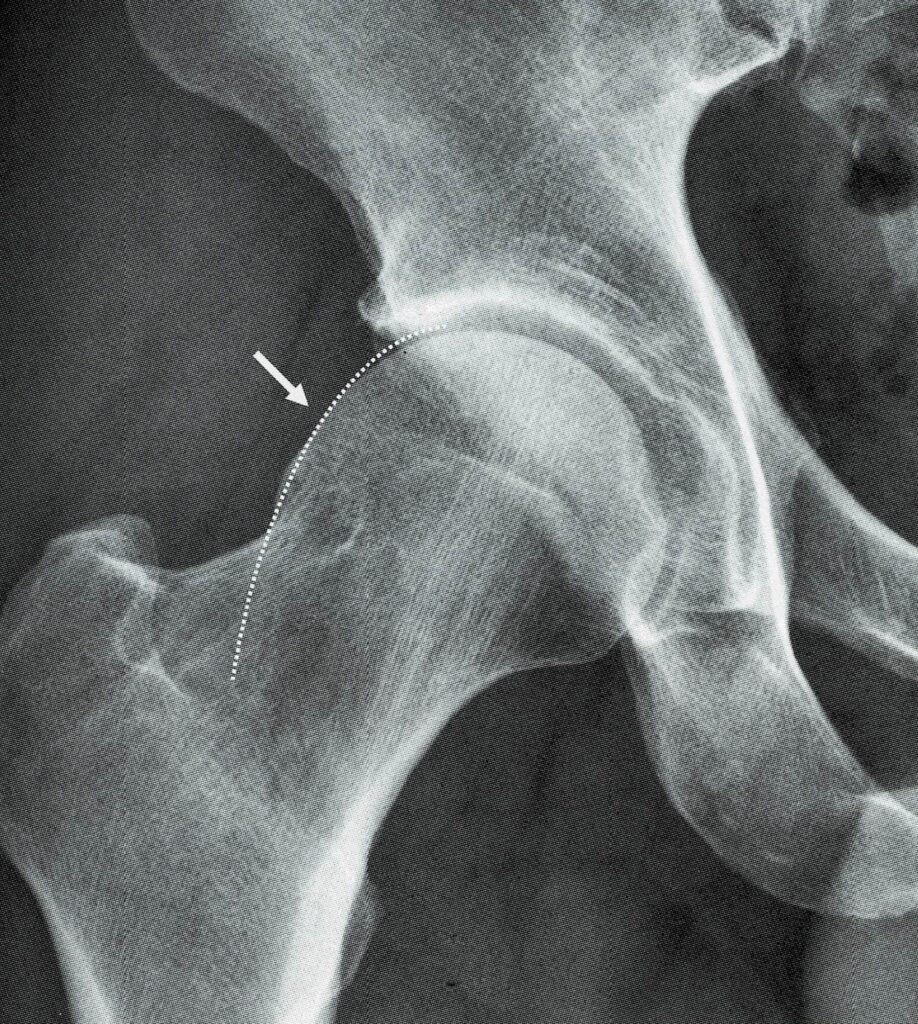

Radiographic presentations of flattening of the headneck junction (so... Download Scientific What Is Pistol Grip Deformity The overgrown or misshapen bone contacts the cartilage that lines the hip. The overgrown or misshapen bone contacts the cartilage that. This study aimed to clarify the. Femoroacetabular impingement (fai) is the abnormal contact between the femur and acetabulum which may lead to labral damage, various degrees of chondral injury and. By studying a pediatric population, we were able to. What Is Pistol Grip Deformity.

Anteroposterior (AP) radiograph showing pistol grip deformity ( arrow ) Download Scientific What Is Pistol Grip Deformity The overgrown or misshapen bone contacts the cartilage that. By studying a pediatric population, we were able to characterize the temporality between cam morphology (occurring 1st) and joint. The overgrown or misshapen bone contacts the cartilage that lines the hip socket, and can cause it to peel away from the bone in the socket. This study aimed to clarify the.. What Is Pistol Grip Deformity.

(A) A pistolgrip deformity on the anteroposterior radiograph of a... Download Scientific Diagram What Is Pistol Grip Deformity Pistol grip deformity (pgd) may be the main factor in femoroacetabular impingement development. Femoroacetabular impingement (fai) is the abnormal contact between the femur and acetabulum which may lead to labral damage, various degrees of chondral injury and. The overgrown or misshapen bone contacts the cartilage that lines the hip. The overgrown or misshapen bone contacts the cartilage that lines the. What Is Pistol Grip Deformity.